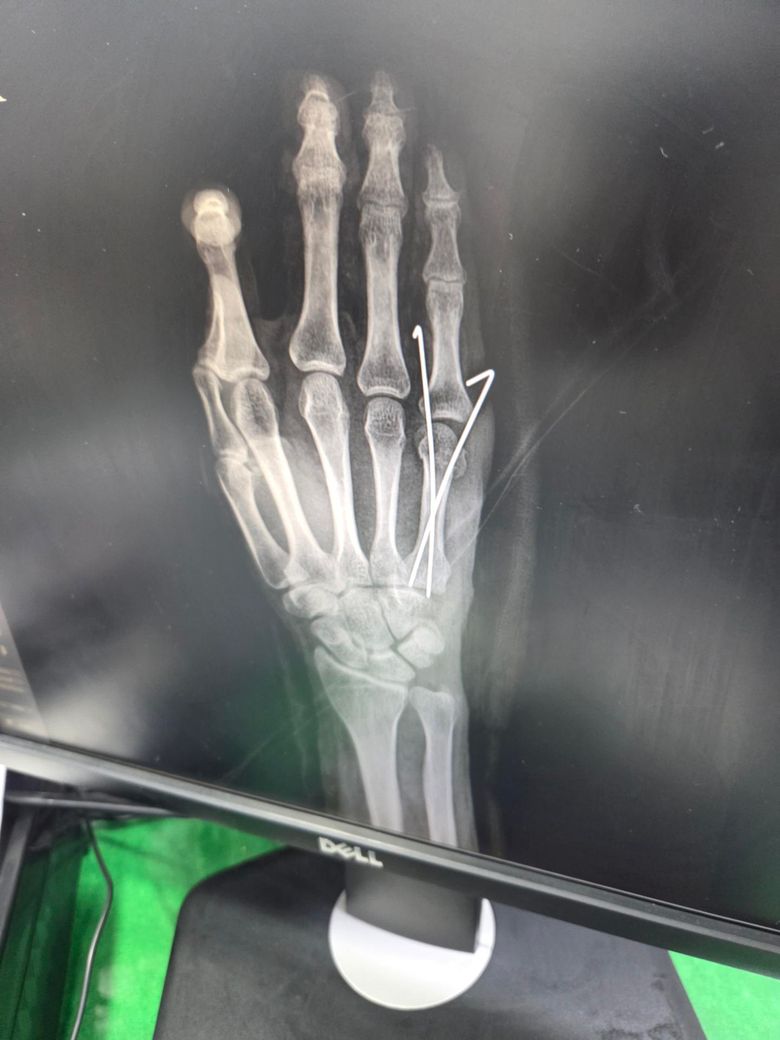

수술 직후 사진이고요

• 3번 째 사진

엑스레이상으로는 금속 핀을 박은 수술로 보이며 사진상 정확한 상태 확인이 어렵긴 하지만 크게 정렬이 틀어지거나 문제는 없는 것으로 보입니다.

우선 현재로썬 수술적인 부분에선 큰 문제가 없어보이지만 사진상 정확히 볼 수 없기에 현재로썬 전문의에 소견을 들어보시길 추천드립니다.

크게 특이소견을 들으신 것이 없다면 수술 시 큰 문제는 없었던 것으로 보이고, 엑스레이상에서도 정렬에 큰 문제는 없는 것으로 보이지만, 우려가되시는 경우에는 다른 병원에서 진료를 받아보시는 것도 좋겠습니다.